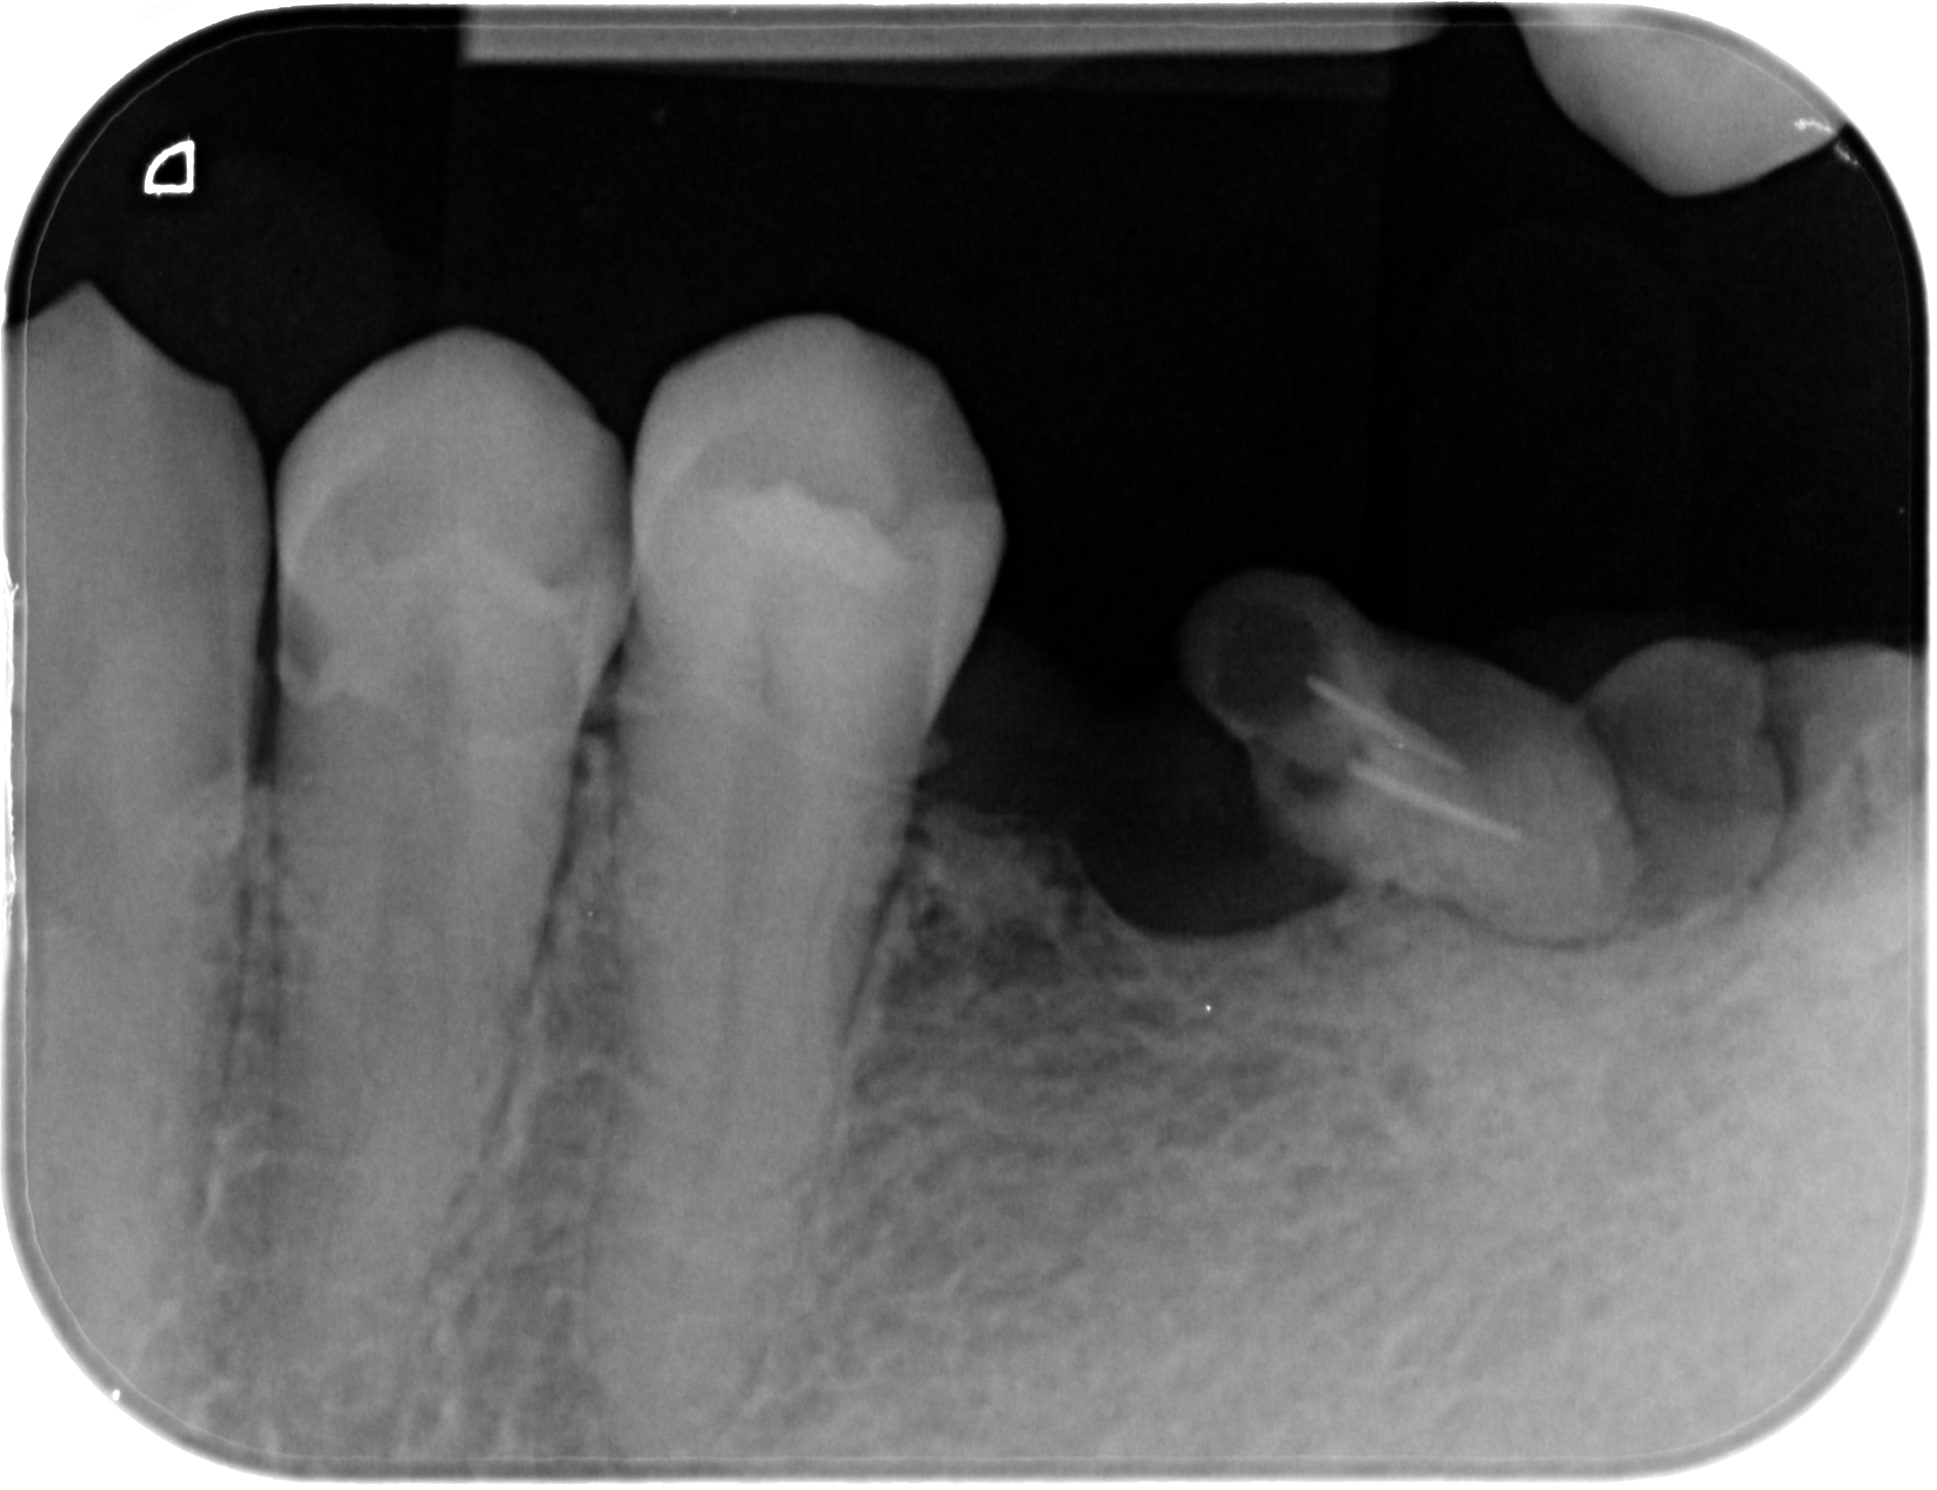

Des comme ça j'en 2 ou 3 par semaine (vu à l'instant ) ... Petite question : quel âge à ce patient ? Deuxième question à Carident et à quelques autres, quel est le montant de votre plan de traitement ? ( je ne demande pas le détail )(@ lardon , la 15 en métal , marqueur social ? ) .. troisième question : pensez vous que ce patient a la mutuelle adéquate à son état dentaire et enfin : pensez-vous que ce patient serait mieux pris en charge grâce au RAC 0 ? On va faire dans le concret de pas mal de cabinet dentaire ....

Pour l'age, c'est pas pour l'expulser, mais c'est impossible à dire par rapport à la radio. Au delà de 18 ans, c'est certain, tu ne sera pas arrêté pour détournement de mineur.

Puisque tu en parles, ca doit être la trentaine. Il a eut différentes extractions réalisées au cour du temps et à abandonné déjà les soins en cours de route.

C'est bien pour cela que c'est impossible de parler de devis et de tarifs, puisque quelque soit le devis, les probabilités d'arriver au bout du plan de traitement sont faible et il abandonnera bien avant les prothèses sur des soins opposables ce qui montre que le tarif et les remboursements ne sont pas en cause.

26/02/2018 à 12h12

Age 19 Ans ! , et bien sûr qu'il ira au bout du traitement s' il peut financièrement ! Il est motivé , c'est un jeune homme "bien" . sérieux , il est à l'heure , n'est pas peureux .. bref , ce genre de patient où tu sais pertinemment que ce qui va coincer c'est l'argent . Barba , il existe des patients non serieux à tous les niveaux de la société et quand c'est un cadre , là , on pense qu'il n'a pas le temps . Alors , on fait quoi pour ce jeune , on le prend en charge ( nous la société ...) ? on lui dit que c'est trop tard ? t'avais qu'à te brosser les dents ? ( vous avez remarqué qu'il a eu déjà de nombreux soins ) . Et, s'il vous plait, gardez pour vous vos généralisations à 2 balles ! ( barba , tu me suis ? ) . Ah ouais aussi , je ne lui ai pas mis un devis sous le nez avant de commencer à le soigner .. évidemment !

Je précise aussi , ce patient n'est pas venu parce qu'il avait mal .... étrange , non ?